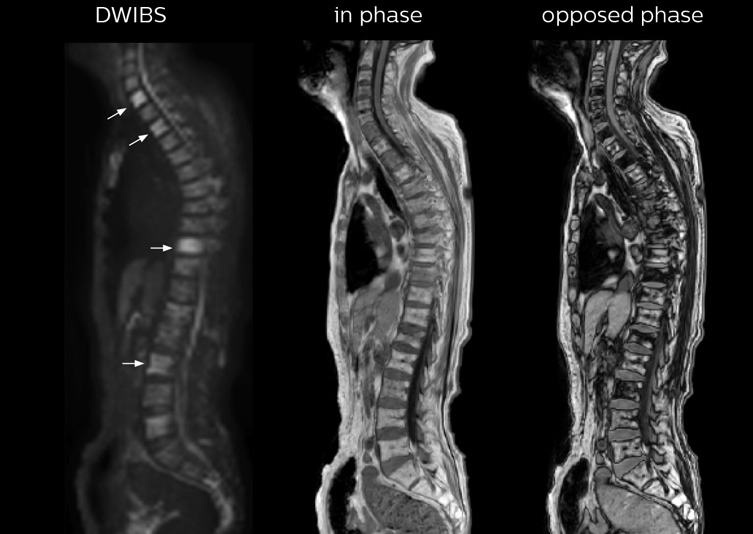

“In-phase and out-phase sagittal T1-weighted FFE images help us to visualize and further characterize bone lesions such as metastasis and bone-marrow hyperplasia that have high signal on DWI. These images are also used throughout radiotherapy, to monitor changes in the fatty bone marrow.”

“mDIXON FFE allows us to quickly get information we need to assess the presence of fat. That gives us more information when we need to diagnose bone lesions, and when we are asked to judge fat-containing lesions such as hepatocellular or renal carcinoma,” Dr. Nobusawa says. “The mDIXON fat images can help us to differentiate fatty bone marrow from bone lesions. This is especially useful in elderly people, who tend to have fattier bone marrow. The water images provide a high signal-to-noise ratio in the intestinal canal, which is valuable for visualizing lesions in the colon,” he says.